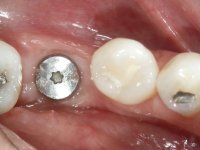

Paciente do sexo feminino, com 36 anos de idade, não fumadora. Apresentava o dente 1.1 com uma tonalidade mais escura que os dentes adjacentes. Feito o exame imagiológico, observou-se que o dente 1.1 tinha tratamento endodôntico, a paciente tinha 3 implantes colocados, dois no local dos dentes 1.2 e 2.2 e o outro no 4.6. A paciente tinha sido tratada ortodonticamente, apresentava um fenótipo gengival médio e uma boa higiene oral. Após 5 anos da primeira intervenção a paciente apresenta-se na consulta com sintomatologia infeciosa compatível com uma peri-implantite nos implantes 1.2 e 4.6. Após exame clínico, foi confirmada imagiológicamente. A perda óssea vertical tinha mais de 4mm nas duas situações.

Após 5 anos da primeira intervenção, a paciente surge na consulta com uma peri-implantite nos implantes colocados no local dos dentes 1.2 e 4.6. Começamos por abordar a peri-implantite no local do dente 2.2. Foi feita uma ponte provisória de laboratório em acrílico com 2 elementos. O dente 1.1 como pilar e o 1.2 como pôntico, este último apresentava um apoio distal. A coroa do 1.2 foi removida do coto com um corte longitudinal feito com turbina e depois foi fraturada com um mini luxador. O coto foi de seguida desaparafusado do implante. Fez-se o mesmo procedimento para remover a coroa do 1.1. O dente 1.1 foi re-preparado e a ponte provisória foi rebaseada em boca com acrílico autopolimerizável. Feito o correto acabamento e polimento da provisória foi feita a sua cimentação temporária com cimento de policarboxylato. Numa consulta posterior. foi feita a remoção da ponte provisória, feita a cirurgia para explantação do implante, colocou-se um novo implante e fez-se a regeneração óssea da zona com uma membrana não reabsorvível. 3 meses após foi removida a coroa do implante colocado no 4.6. Foi feito um corte horizontal com turbina na zona cervical e com um mini luxador descolou-se a coroa do coto. Após este procedimento fez-se a explantação do implante. Após 6 meses foi colocado um novo implante no local do 4.6. Após a osteointegração foi feita a impressão com a técnica de moldeira aberta e foi confecionada em laboratório uma coroa aparafusada sobre o implante. Aprovada pela paciente foi apertada definitivamente em boca. Após 1 mês removemos a ponte provisória antero-superior, reforçamos o dente 1.1 com um poste intra- radicular e reconstruimos o coto com uma resina de polimerização dual. Nessa mesma consulta expomos o implante colocado no 1.2 e fizemos uma impressão pela técnica de moldeira aberta com silicone de dupla viscosidade e presa rápida. No laboratório foi feita uma ponte provisória de 2 elementos, aparafusada sobre o implante e cimentada sobre o dente. A primeira ponte provisória foi removida e colocada a segunda aparafusada sobre o implante. A linha de acabamento cervical do 1.1 foi rebaseada com resina composta durante o aperto do parafuso do implante. Depois foi removida, foram feitos os acabamentos e finalmente apertada sobre o implante e cimentada temporariamente sobre o dente. Após 2 meses de maturação dos tecidos moles em função do perfil de emergência criado pela nova ponte provisória, pudemos avaliar a estética conseguida em conjunto com a paciente. Neste longo processo o dente 2.1 teve que fazer um tratamento endodôntico. Decidiu-se assim fazer também uma coroa no dente 2.1.O dente 2.1 foi preparado na mesma consulta em que se fez a impressão ao implante. A ponte provisória foi utilizada para individualizar a peça de transferência, copiando o seu perfil de emergência e em seguida foi realizado o afastamento gengival com caolino. A impressão foi feita com a técnica de moldeira aberta com silicone de dupla viscosidade e presa rápida. Após a escolha da cor, a impressão foi enviada  para o laboratório onde foram confecionadas 2 coroas  com infraestrutura em Zr. revestidas a cerâmica para os dentes 1.1 e 2.1 e uma coroa aparafusada sobre o implante no dente 1.2. O trabalho final foi aprovado pela paciente e foi colocado definitivamente em boca. A coroa sobre o implante foi aparafusada com 35 N e as coroas foram cimentadas com cimento de ionómero de vidro reforçado com resina.